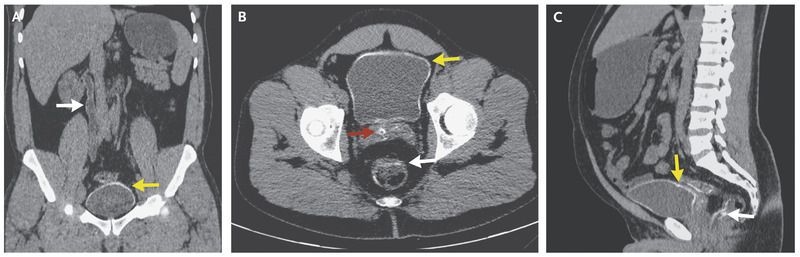

A 43-year-old man presented with a 1-month history of dysuria and intermittent hematuria. Similar episodes had occurred several times in the 6 months preceding presentation, along with episodes of rectal bleeding. The physical examination was unremarkable. Laboratory investigations revealed an elevated albumin:creatinine ratio (96 mg of albumin per millimole of creatinine), with dysmorphic red cells in the urine. Two urine cultures were sterile. A serum schistosoma antibody titer was 1:256. Renal ultrasonography revealed mild hydroureteronephrosis. Computed tomography of the abdomen and pelvis without the administration of contrast material revealed hydroureteronephrosis of the right ureter and kidney, with faint mural calcification of the ureter (Panel A, white arrow) and smooth mural calcification of the bladder (Panels A, B, and C, yellow arrows). There was also calcification of the seminal vesicles (Panel B, red arrow) and the wall of the rectosigmoid bowel (Panels B and C, white arrows). This pattern of calcification is typical of chronic genitourinary and gastrointestinal schistosomiasis, in which the larvae of the schistosoma parasite are deposited on the walls of the organs and become calcified. Diagnosis is based on a history of exposure along with a strong clinical suspicion of infection and the characteristic radiographic findings. Tuberculosis may also cause calcification of the bladder wall and should be considered in the differential diagnosis.